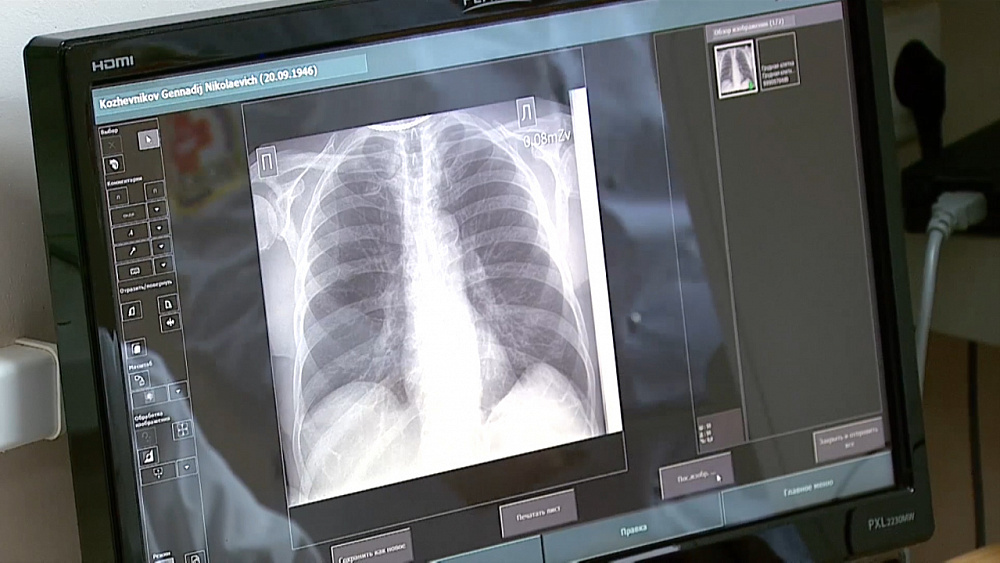

Легкие — это важный орган в нашем организме. Именно они обеспечивают нормальное дыхание. Если что-то беспокоит — затрудненное дыхание, одышка, кашель, обычно сначала врач слушает легкие через стетоскоп. На втором этапе уже применяются технические средства: рентген и КТ, а также ряд специальных процедур, позволяющих оценить объем и газообменные процессы в легких. Один из этих методов — спирометрия. Что это за исследование и как оно проводится?